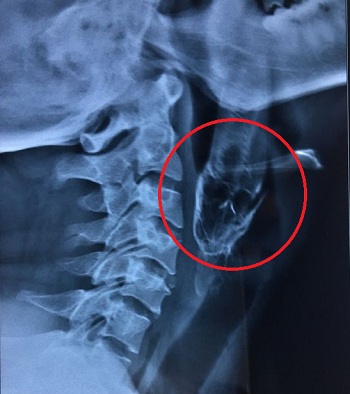

Chụp phim cho thấy phần đầu con cá đã chui vào họng Dash, phần đuôi của nó kẹt sâu trong miệng anh ta. Bác sĩ phải gây tê tại chỗ và dùng kẹp gắp con cá ra.

Con cá bị mắc kẹt dài đến 11cm.